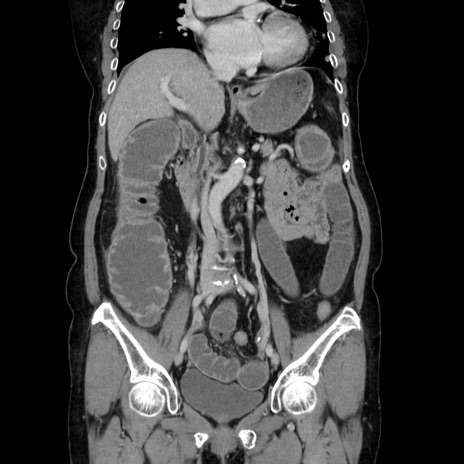

症例5(冠状断像)

【症例】70歳代女性

【主訴】お腹が張る

【現病歴】1週間くらい前から腹部膨満の自覚あり。昨日夜から増悪したため、本日救急外来受診。

【身体所見】意識清明、BT 36.5℃、BP 165/106mmHg、HR 80bpm、SpO2 98%、腹部:膨満、軟、自発痛・圧痛なし、触診にて不快感あり、腸蠕動音:減弱

【データ】WBC 12600、CRP 1.04